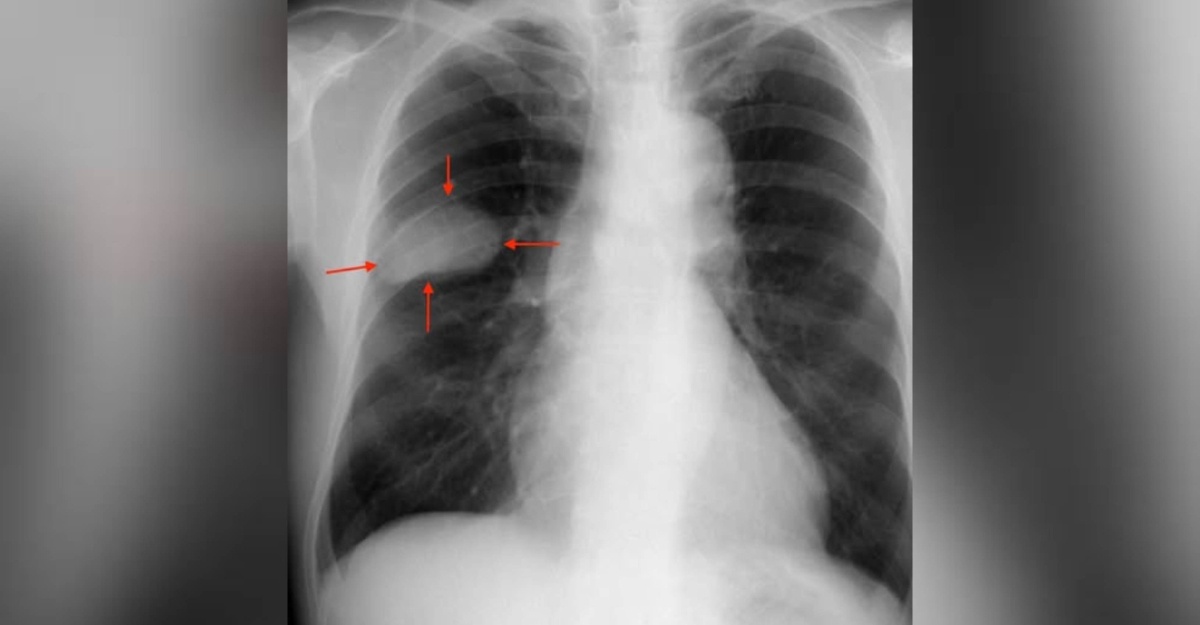

Aku mendengar bunyi pernafasannya dengan teliti. Ada sedikit bunyi ‘wheezing’. Aku mengambil keputusan untuk membuat X-ray sebagai langkah berjaga-jaga.

Keesokan harinya, keputusan X-ray keluar. Ada bayang-bayang pada paru-paru kanannya.

Aku segera mengatur CT scan dan biopsi. Dan akhirnya, kepastian itu tiba—sesuatu yang tidak mahu didengar oleh sesiapa pun.